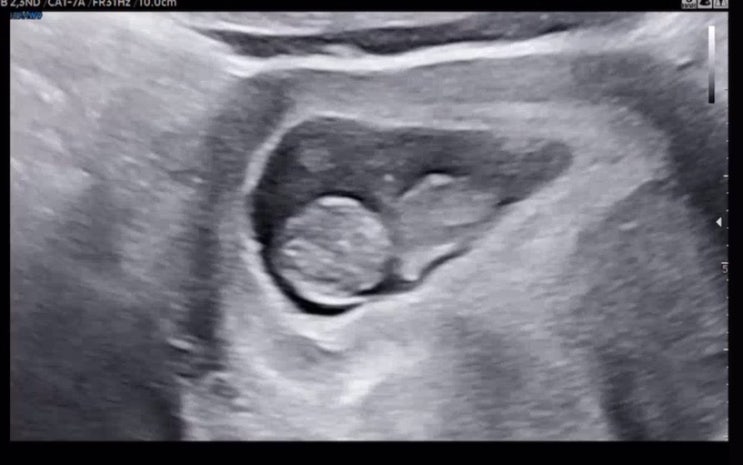

[젠또일기] 임신16주차 검진 (성별 확인, 2차 기형아 검사), 입덧 사라짐

임신 16주 새해 시작과 함께 젠또는 벌써 5개월차인 16주 입성 ! 5개월차라니... 신기하다.. 16주 1일에 16...

[젠또일기] 임신 6주 ~ 10주차 일상 (심장소리, 젤리곰)

임신 6주차 6주차부터 아침에 무언가를 챙겨먹기 시작함 고구마, 두유, 포도즙, 빵 등 아침을 챙겨다녔다. ...